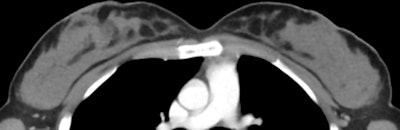

Salavatore's group conducted a pilot study comparing radiologists' readings of breast density at CT of the chest with breast density readings from mammography performed in the same patient (Radiology, October 14, 2013).

The study included mammograms and chest CT scans acquired within one year of each other in 206 women, between 2007 and 2011. Two radiologists reviewed the mammograms and CT scans and classified each case into one of the four breast density types defined by BI-RADS.